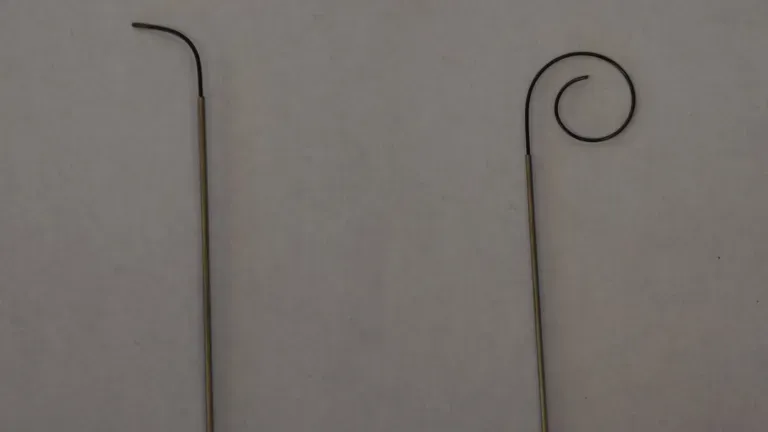

This project involves a new class of steerable needle insertion where the objective is to first control the direction of tissue fracture with an inner stylet and later follow with the hollow needle.

A variety of inner stylet geometries are investigated using tissue phantoms with multiple stiffnesses and discrete-step kinematic models of motion are derived heuristically from the experiments.

The key finding presented is that it is the geometry of the stylet and the tuning of the bending stiffnesses of both the stylet and the tube, relative to the stiffness of the tissue, that allow for such a small radius of curvature even in very soft tissues.